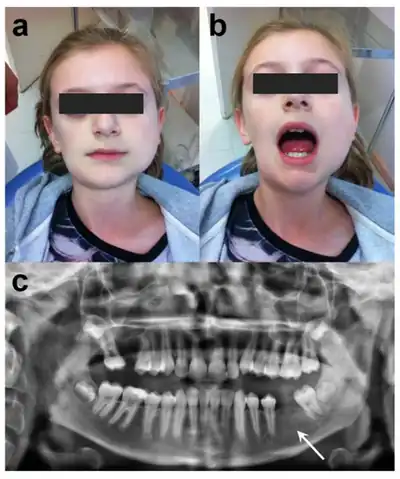

| a) Frontal view b) limited mouth opening of 25 mm, c) panoramic radiograph | |